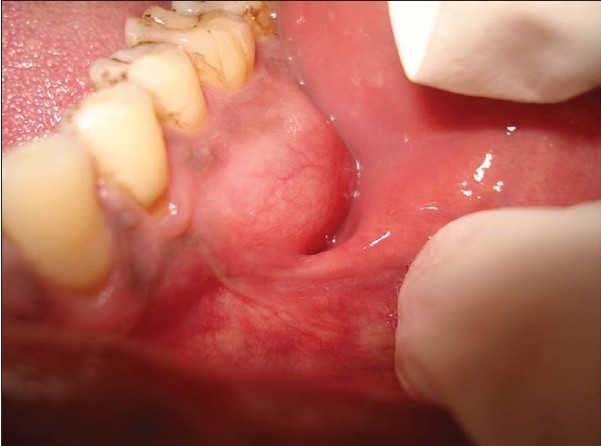

It's critical to thoroughly brush the area where the gums meet the teeth and floss between the teeth to keep the entire gingival sulcus clean. When plaque is allowed to build up on the gums at the base of a tooth, it can cause gingivitis, when the gums become inflamed and irritated. Luckily, you can reverse gingivitis with excellent oral care. However, if the plaque continues to build, the inflammation can lead to the gums detaching from the tooth, causing the space between the teeth and gums to deepen and allow even more plaque to accumulate. This deepening of the sulcus, also referred to as the development of a periodontal pocket, is an early indicator for periodontal disease. The National Institute of Dental and Craniofacial Research classifies periodontal disease as a site with gum attachment loss of at least 3 millimeters and a pocket depth of at least 4 millimeters.

When plaque has packed into and invaded the gingival sulcus, further complications can arise, such as tooth loss. To stop the damage, your dental professional may recommend a more involved type of dental procedure called scaling or root planing to access the area under the gumline. If the damage caused by the bacteria is more severe, a dental professional can improve the health of the gums with surgical methods, such as a gum graft.